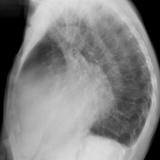

Ao valve calcif (lat only)

Date: 01/26/2009

Views: 2739